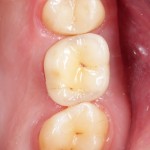

На приведенных фотографиях заметно, как изменились линейные размеры альвеолярного гребня с момента удаления 26 и установки импланта, до его интеграции (сравните толщину). Но это не так критично, и позволяет получить хороший результат протезирования:

Однако, если одной из задач имплантологического лечения является максимальное сохранение окружающих зуб тканей, то без использования биоматериалов вряд удастся обойтись. На фотографии ниже: вроде как, проведена немедленная имплантация, но последующая атрофия альвеолярного гребня вконец испортила эстетический результат лечения.